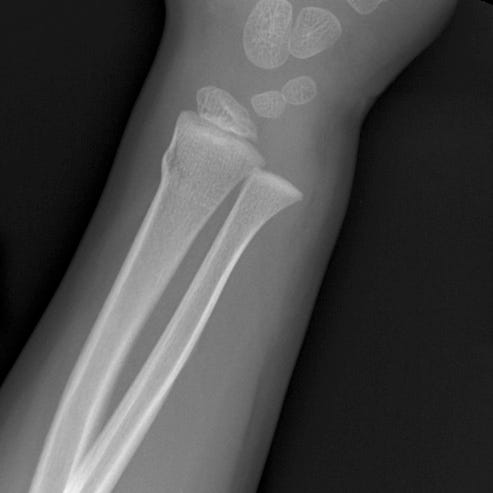

Forearm buckle or torus fractures are common in children and are usually due to falling on an outstretched arm. Force transmitted along the extremity axis results in compression of trabecular bone and bulging of the adjacent cortex without a distinct fracture line. Subtle cortical buckling or angulation may be the only radiographic finding. Common symptoms are pain, tenderness, swelling, and inability to rotate the forearm.

Buckle (torus) fracture. Mild cortical buckling along the dorso-radial aspect of the radial metaphysis. No displacement or angulation.

While radiographs are typically obtained, ultrasound can also be used for diagnosis. Treatment consists of immobilization and prompt orthopedic follow-up. These fractures have a good prognosis, and com- plications are rare.